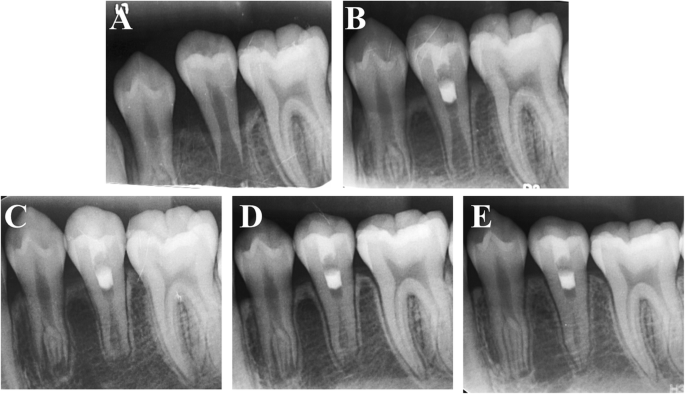

a A periapical radiograph of #45 with apical periodontitis in a 12-year-old girl. In #45, conventional RET was performed. b Three-month follow-up periapical radiograph. c Six-month follow-up radiograph. d Nine-month follow-up radiograph. e Twelve-month follow-up radiograph showing healing of the periapical lesion and root development

a An intraoral periapical radiograph of a 12-year-old girl showing a wide-open apex of #45 with thin lateral dentinal walls and apical radiolucency. b Three-month follow-up periapical radiograph of tooth #45 after undergoing conventional RET. c Six-month follow-up radiograph. d Nine-month follow-up radiograph. e Twelve-month follow-up radiograph showing apical radiolucency resolution, apex closure, root elongation and lateral dentinal wall thickening